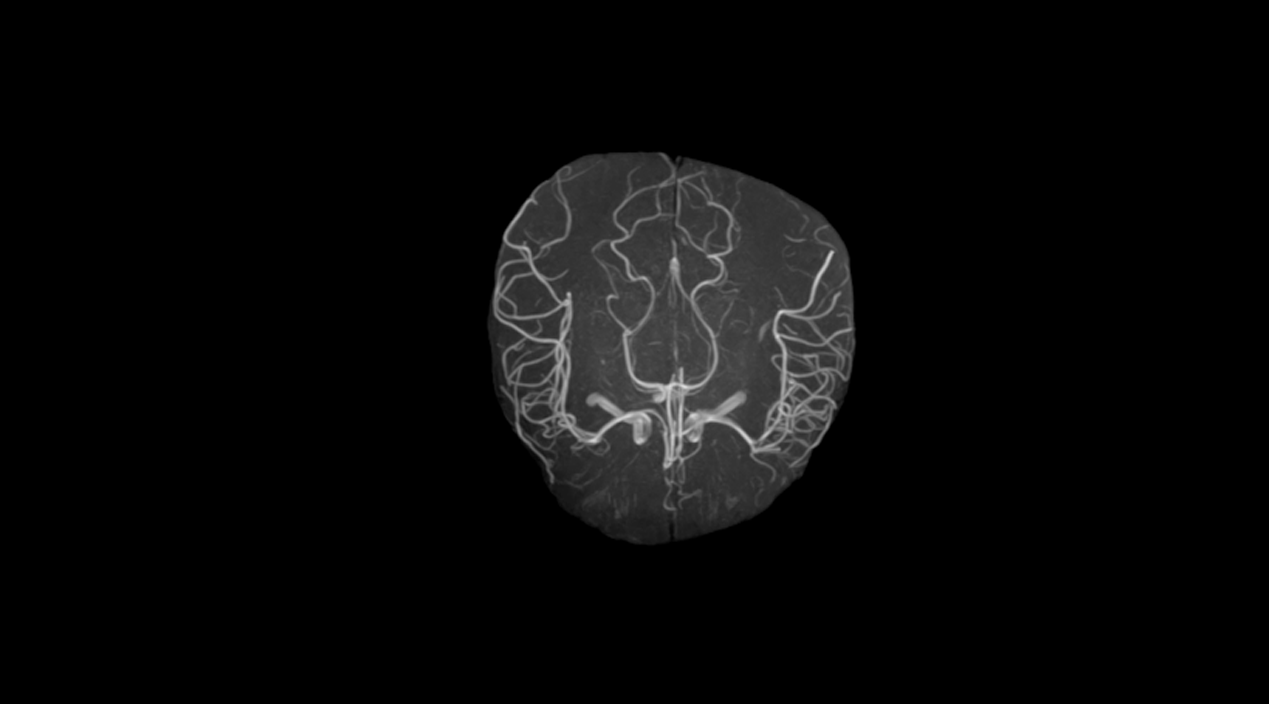

1.5T MRI

Kangda Colorful Model: Farol 1.5T

Product Introduction

Product highlights

1.5T superconducting magnet technology: using "Zero Boil-off " superconducting magnet technology;

Fine shimming system: Adopting a fine shimming system to maximize theeffectiveness of the magnet;

16 channel fiber optic RF signal digital transmission technology: Advancedfiber optic RF signal digital transmission technology is sampled to eliminatesignal loss and distortion caused by MR signals during transmission;

CS compression perception acceleration function: greatly improvesscanning speed while ensuring image quality;

High performance gradient system: Adopting a high-performance gradient system with a maximum intensity of 35mT/m, extremely low vortex flow ensures image clarity;

Artificial Intelligence Scanning Assisted Diagnosis Technology;